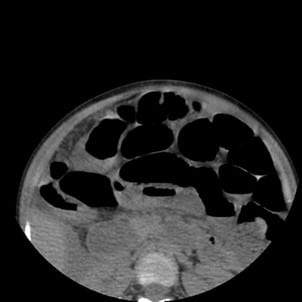

A plain CT of the abdomen was also taken to confirm the diagnosis before being taken to surgery. It showed dilated bowel loops, a radiopaque mass possibly fecalith or appendicolith, and an Inflamed and enlarged appendix. After taking the symptoms, signs, and investigations into consideration, the child was diagnosed with Appendicitis with small bowel obstruction and fecal impaction and taken to surgery. Figures 7 to 9 below show the CT images, axial section of the lower segment of the abdomen.

Figure 7: CT image of axial section of lower segment of abdomen showing dilated bowel loops

Figure 8: CT image showing radiopaque mass, possibly fecalith or appendicolith

Figure 9: CT image showing an inflamed and enlarged appendix with a possible faecolith or appendicolith